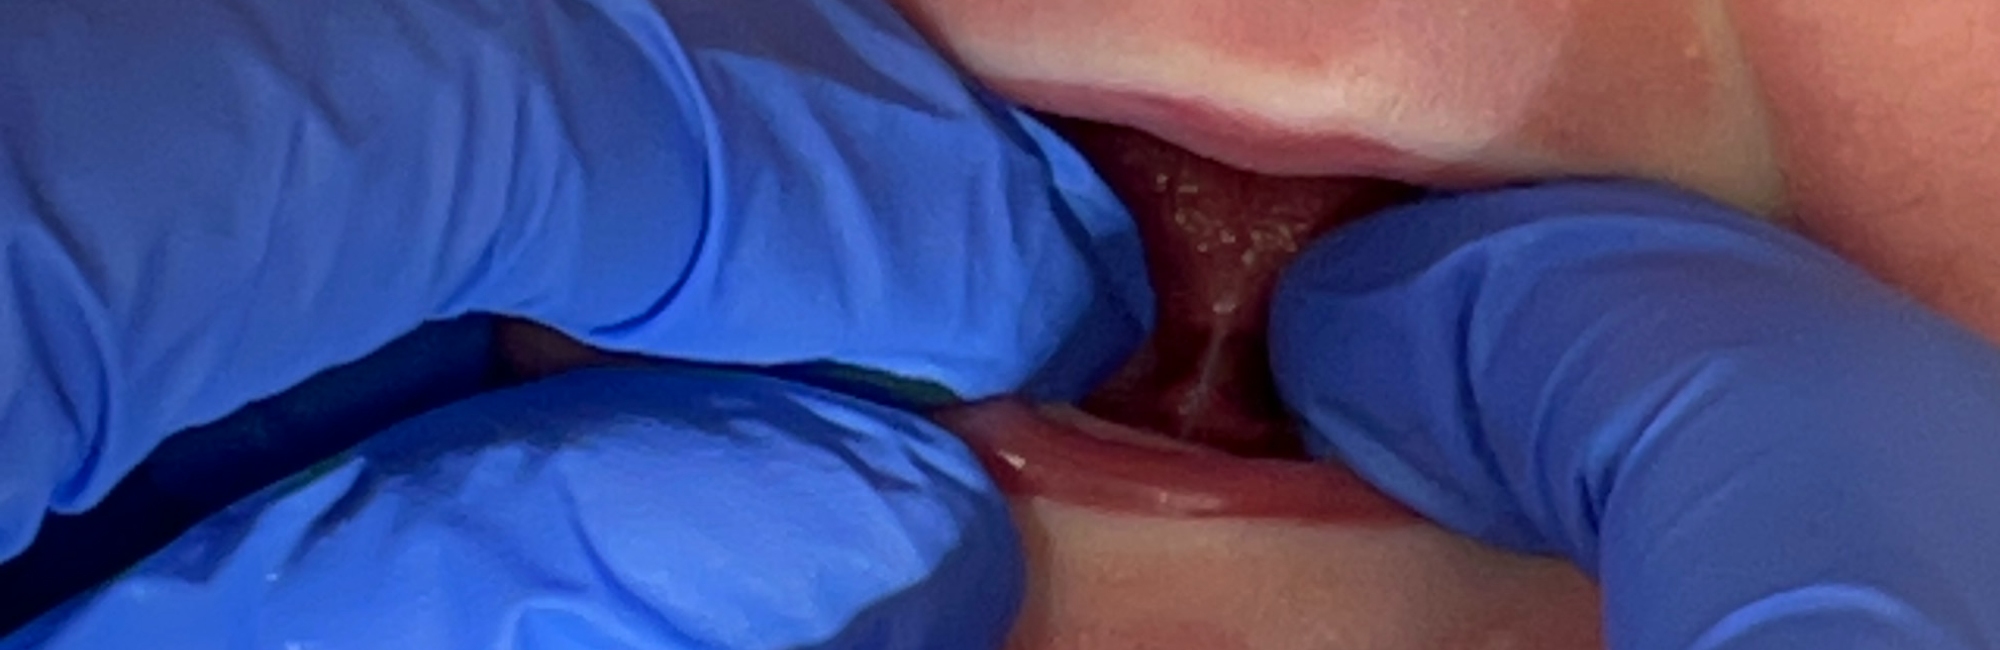

C. The photo below also displays the lingual frenulum. The frenulum inserts well behind the alveolar ridge.